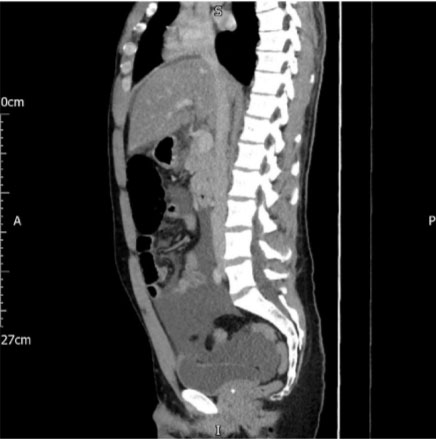

The CT scan showed a defect at the dome of the urinary bladder measuring approximately 1.5 cm in diameter. A large amount of free fluid in the abdomen and pelvis was present, likely due to, intraperitoneal rupture of the urinary bladder with urine extravasation (Figure 1 and Figure 2).

Figure 1: Coronal section of CT scan abdomen and pelvis showing an intraperitoneal bladder rupture.

Share Image:

Figure 2: Sagittal section of CT scan abdomen and pelvis showing an intraperitoneal bladder rupture.